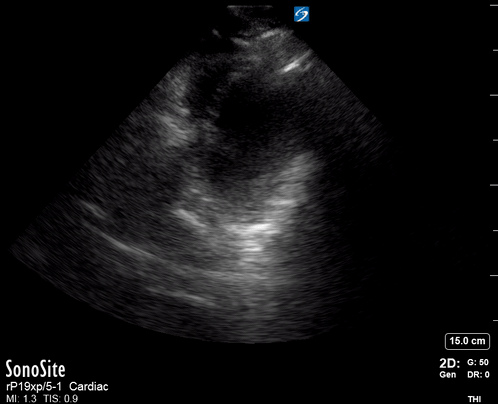

Effusion: is there a pericardial or pleural effusion?

Pericardial effusion is a continuum and can potentially evolve into haemodynamic collapse. Tamponade physiology is detectable earlier with ultrasound than with traditional physical examination, and it has been demonstrated that PoCUS improves mortality in penetrating cardiac trauma. Timely and accurate diagnosis is, therefore, vital.

THE VIEWS

The subxiphoid view is the most reliable for detecting pericardial effusion. Still, it is ideal to obtain different views not to miss a focal effusion as small amounts of fluid can lead to tamponade physiology. Tamponade does not link strictly to the size of the effusion, but correlates more with the speed of onset, causes, and haemodynamic effects.

PITFALLS & PLEURAL EFFUSIONS

A common error is to confuse a pericardial fat pad with effusion. Fatty tissue has a heterogeneous echotexture, moving in coordination with the myocardium, and it cannot be tracked around the heart, especially posteriorly and to the apex. Another pitfall is misinterpreting a pleural effusion as a pericardial effusion. However, they can be differentiated by their relationship to the descending aorta. Pericardial effusion may be seen between the aorta and the LV free wall, whereas pleural effusions are posterior to the descending aorta. Lastly, other causes, namely hypovolaemia and large pleural effusions, can cause RA and RV collapse.

CARDIAC TAMPONADE

Progressively rising pressure translates into evolving tamponade, and this accompanies a series of ultrasound findings:

Initially, the RA collapses during ventricular systole (closed AV valves).

Followed by RV collapse in ventricular diastole (open AV valves).

Ultimately leading to LV collapse.

In addition, the presence of a non-collapsible, plethoric IVC is one of the most sensitive signs of tamponade, and a finding easy to visualise. Conversely, a pericardial effusion in a haemodynamically stable patient with a collapsible IVC is unlikely to represent tamponade.